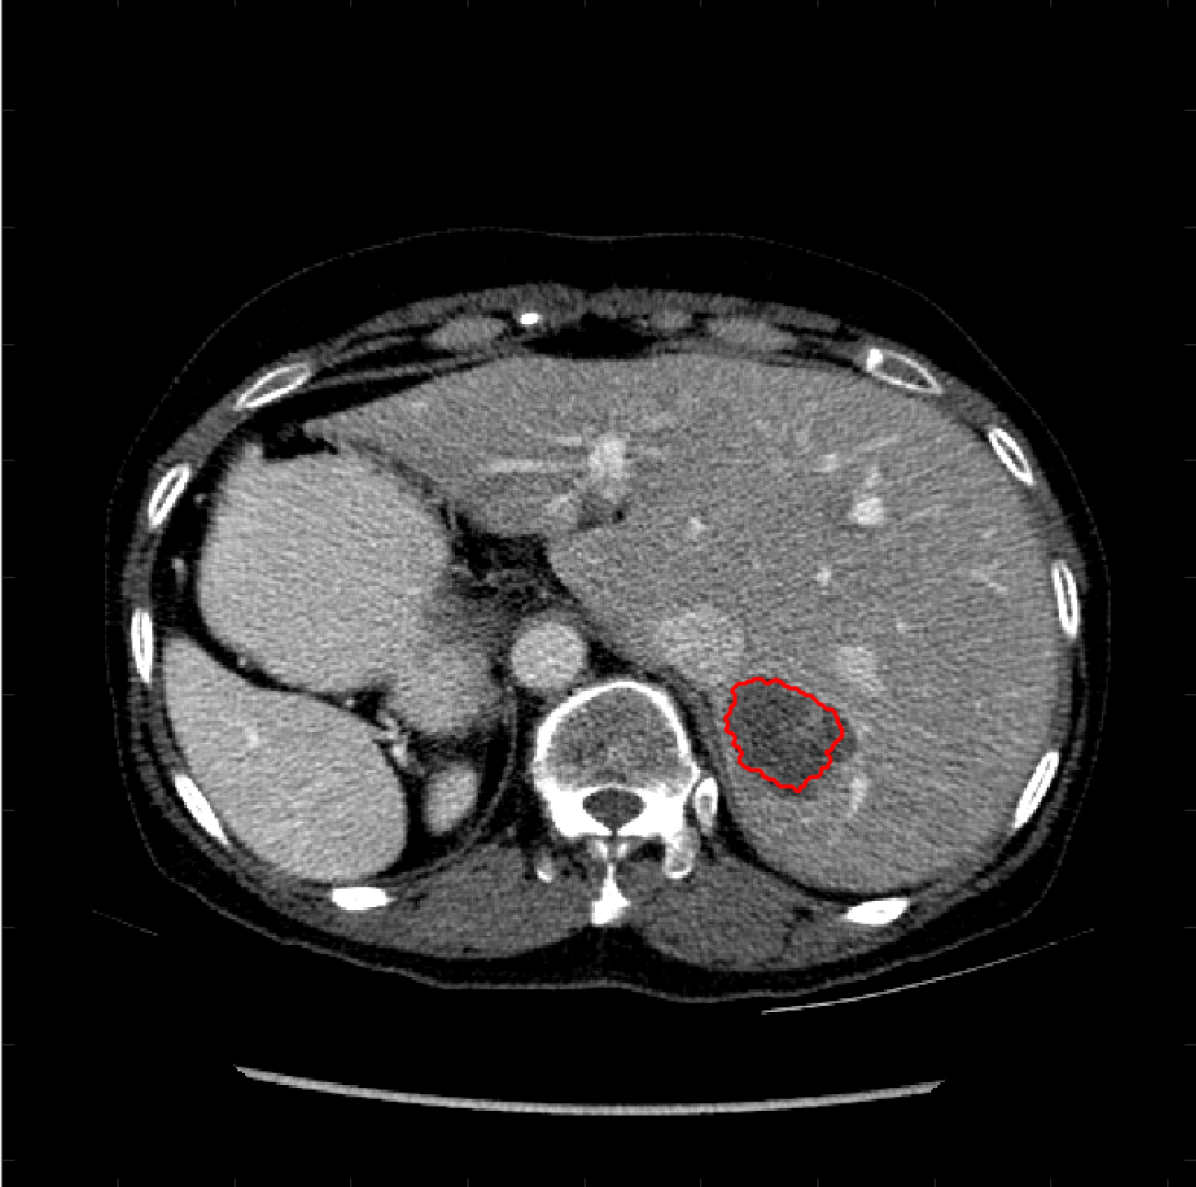

Figure 5: A sample result on the Liver data. We display the input image with the user input \mathcal{M}, the ground truth (GT) and results from the four methods. Moreover, we show comparisons with the model (4) solved in a variational framework with both Total Variation (TV) and Euler Elastica as explicit regularisation, as well as a comparison with the model solved in a Deep Image Prior framework.

Similarly we show some results in Figures 5 and 6 from the LiTS dataset of all the methods. Quantitative results of the 272727 images can be found in 2. Clearly for both datasets, M3 and M4 using the proposed ideas outperform M1 and M2, as well as methods using explicit regularisation (TV and Elastica), and the original DIP method.